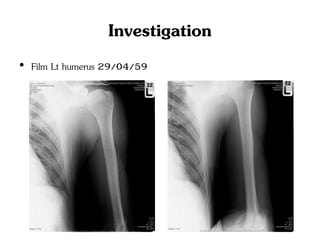

• Film Lt humerus 29/04/59

Investigation